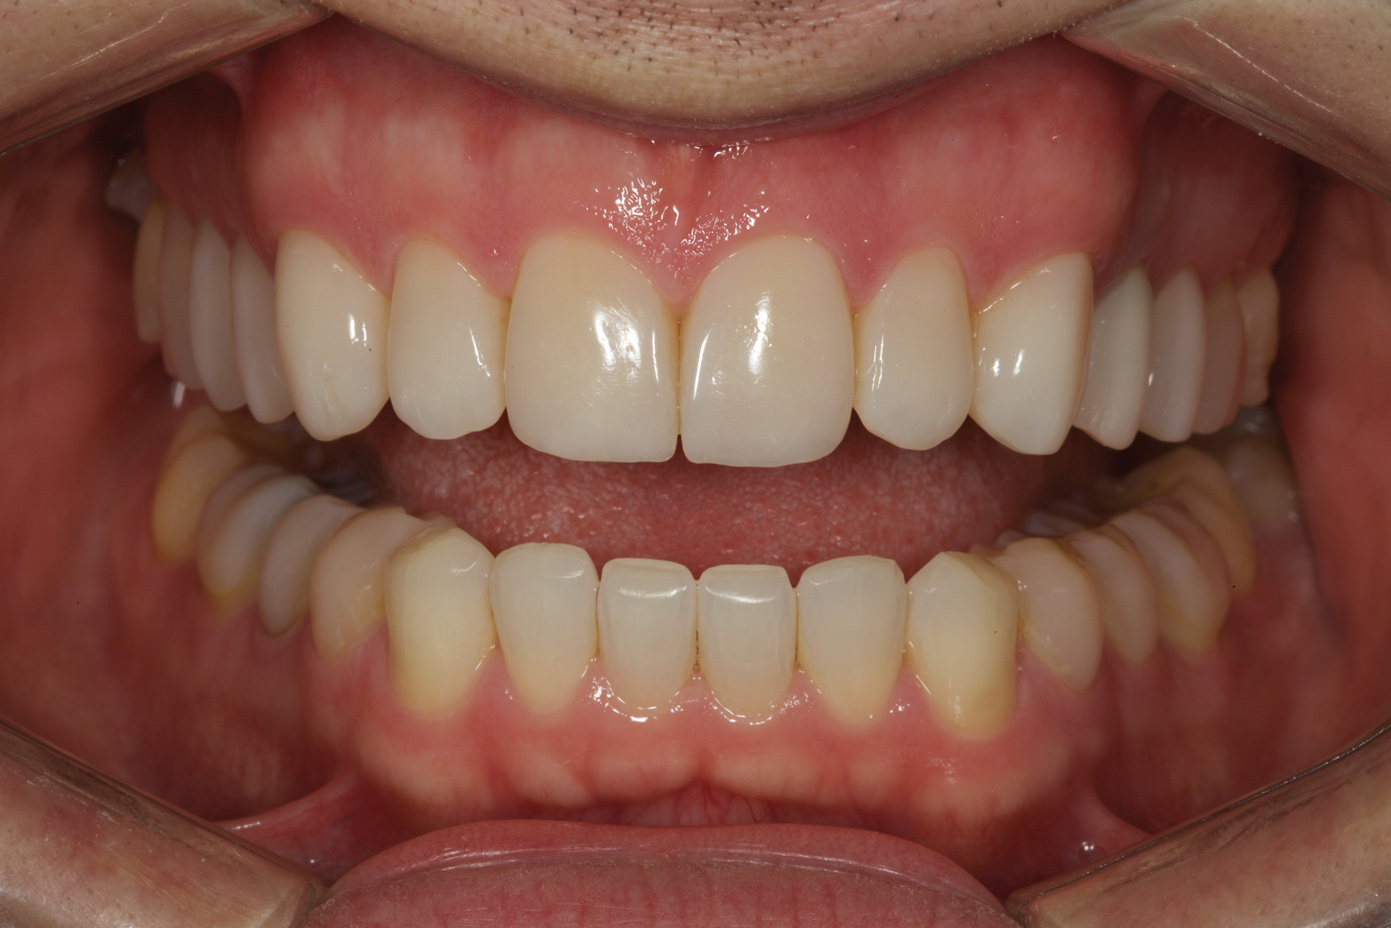

A 34-year-old male patient with no medical issues presented to the office with the chief complaint of a failing crown on tooth No. 12. The patient was also unhappy with his bite and the appearance of his teeth (Figure 1 and Figure 2).

A comprehensive examination was carried out, and preoperative photographs were taken (Figure 1 through Figure 4). The patient presented with fair oral hygiene and slight, generalized tissue inflammation. Caries and defective restorations were detected on teeth Nos. 4, 5, 13, and 14. The crown on tooth No. 12 was showing signs of leakage, and although the endodontic access cavity had been temporarily restored with composite, this endodontic re-treatment was acceptable and the tooth was otherwise symptom-free. Erosion was present on most of the posterior teeth and the cuspids, and abrasion was noted on teeth Nos. 4, 5, 10, 11, 20, 21, 22, 28, and 29. An examination of the patient's muscles, joints, and bite revealed no joint sounds, a normal range of motion, and negative joint load and immobilization tests.

The patient's removable dental orthotic covered the lower bicuspids and first molars. With the orthotic in place, there was shim stock contact on all posterior teeth and on the second molars that were not covered by the appliance. However, there was no incisal overlap and a lack of anterior guidance.9When the orthotic was removed, no more than three teeth touched, and a 2-mm space between the posterior teeth made mastication difficult.

The dentofacial examination revealed a low smile line with no incisor display when the lips were in repose. The anterior teeth were chipped and worn, and their overall color was darkened. The buccal corridors were deficient, and the failing crown on tooth No. 12 was visible in a full smile.

Fig 2. Preoperative retracted view.

Figure 2